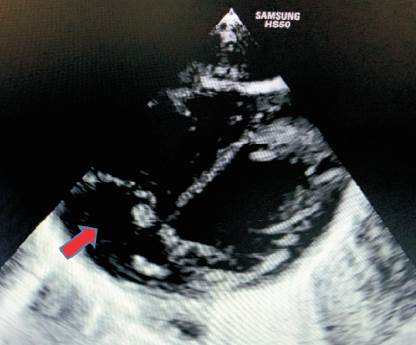

A los 14 días de vida se observa lesión en topografía de inserción de catéter percutáneo, solicitándose hemocultivo, nuevamente positivo a S. epidermidis, por lo que se decide inicio de vancomicina. En este contexto se realiza diagnóstico de endocarditis sobre válvula nativa, en válvula tricúspide en corazón sin patología estructural, de acuerdo a lo criterios de Duke modificados (Figura 1). Se realiza tratamiento con vancomicina durante 6 semanas y control con ecocardiografía (Figura 2) (Tabla 1). Desaparición macroscópica de la vegetación a los 54 días de vida (Tabla 2).